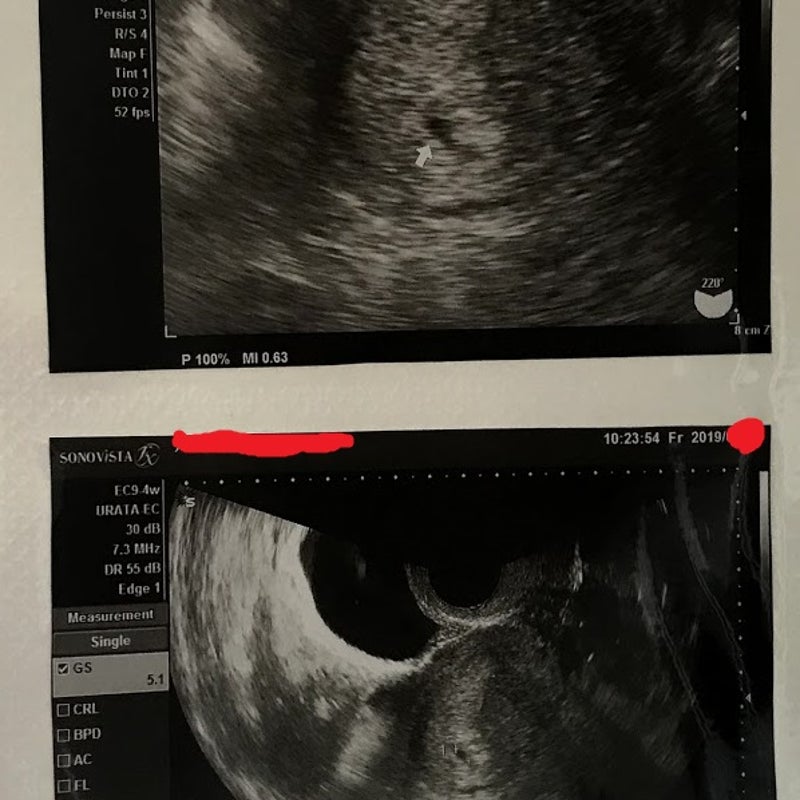

胎嚢の大きさの平均ってどれくらいなの ママリ

胎嚢 たいのう の大きさの平均は 妊娠5週 6週 7週の目安は 週数別に解説 ままのて

妊娠5週の胎嚢確認について エコー写真あり 教えていただければ幸いで 妊活 教えて Goo